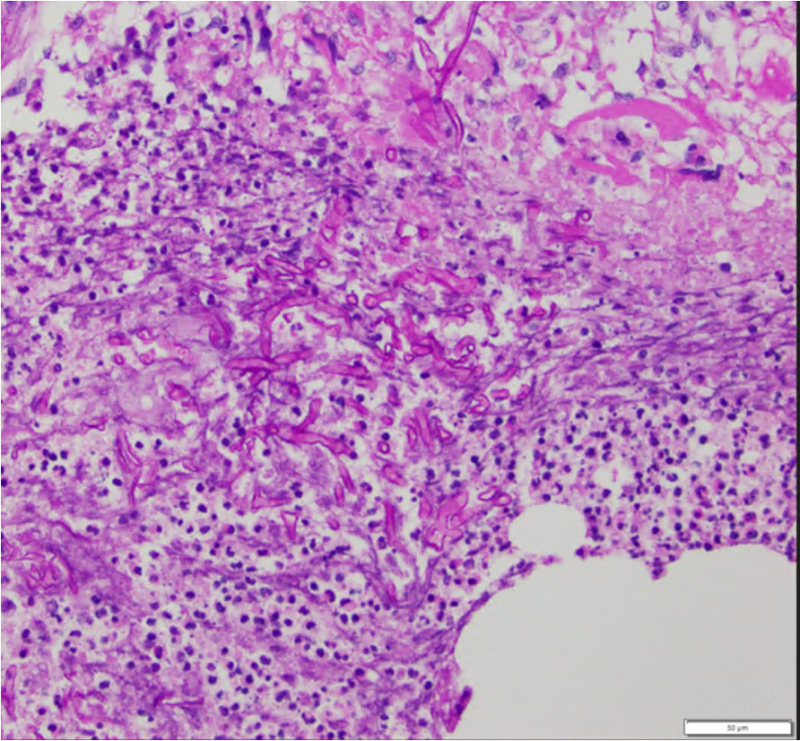

Imaging studies may include CT/MRI of orbit, brain, and sinuses demonstrate involvement of maxillary and ethmoid sinus, orbit, cavernous sinus, and less frequently involve the frontal and sphenoid sinus. In order to obtain a true diagnosis of mucormycosis, a fine needle aspiration biopsy of infected tissues must be obtained for histopathology and culture. Characteristic of this disease is aseptate hyphal elements that branch at right angles. [13]

Finally, the gold standard diagnostic procedure is biopsy and culture. Histopathological confirmation included H+E (hematoxylin-eosin), PAS (periodic acid-Schiff) and GMS (Grocott-Gomori's methenamine silver stain), among others.